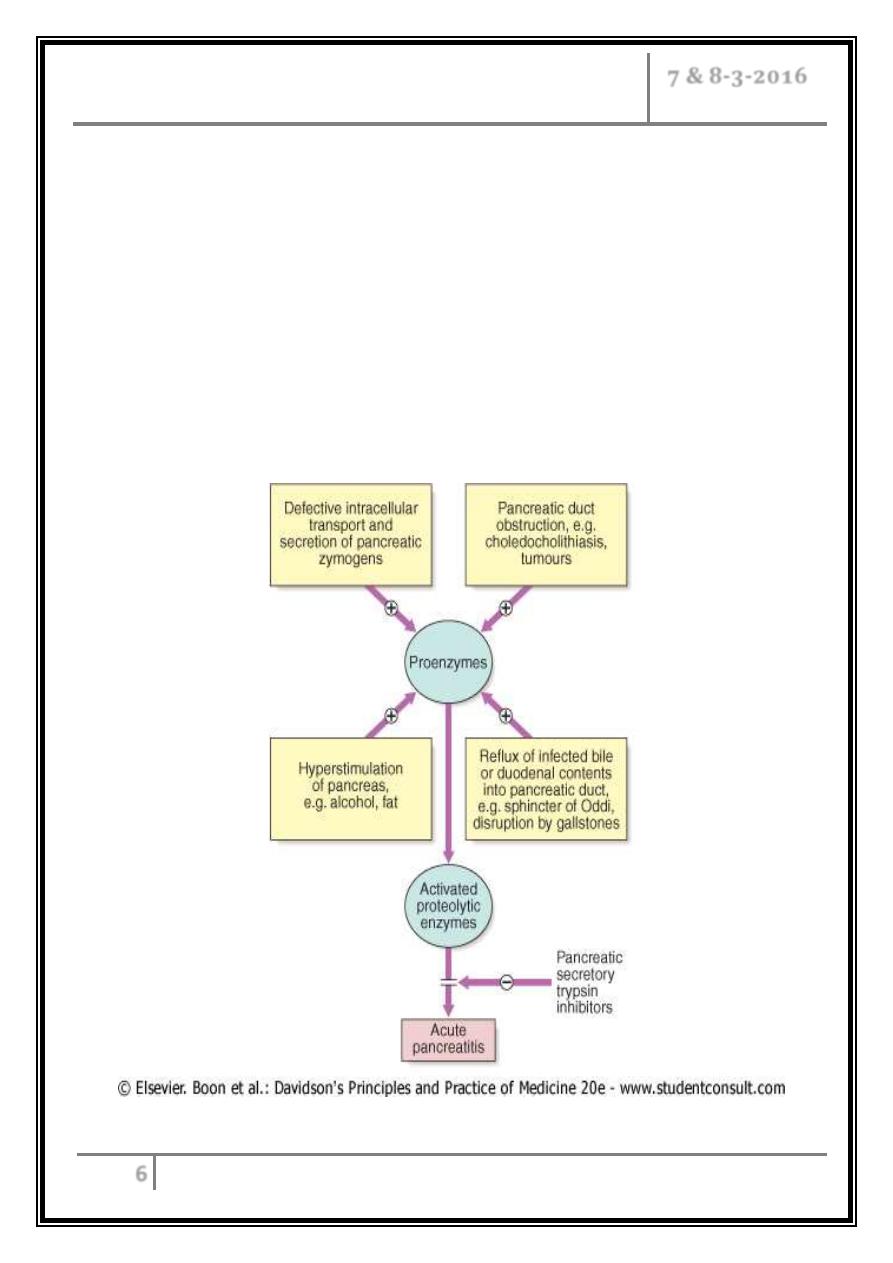

Pathophysiology

o Acute pancreatitis occurs as a consequence of premature activation of zymogen

granules, releasing proteases which digest the pancreas and surrounding tissue.

o The severity of acute pancreatitis is dependent upon the balance between

activity of released proteolytic enzymes and antiproteolytic factors.

o Acute pancreatitis is usually mild and self-limiting, with minimal organ

dysfunction and uneventful recovery. In some patients, however, it is severe,

with local complications such as necrosis, pseudocyst or abscess, and systemic

complications leading to multi-organ failure.

Pathophysiology of acute pancreatitis